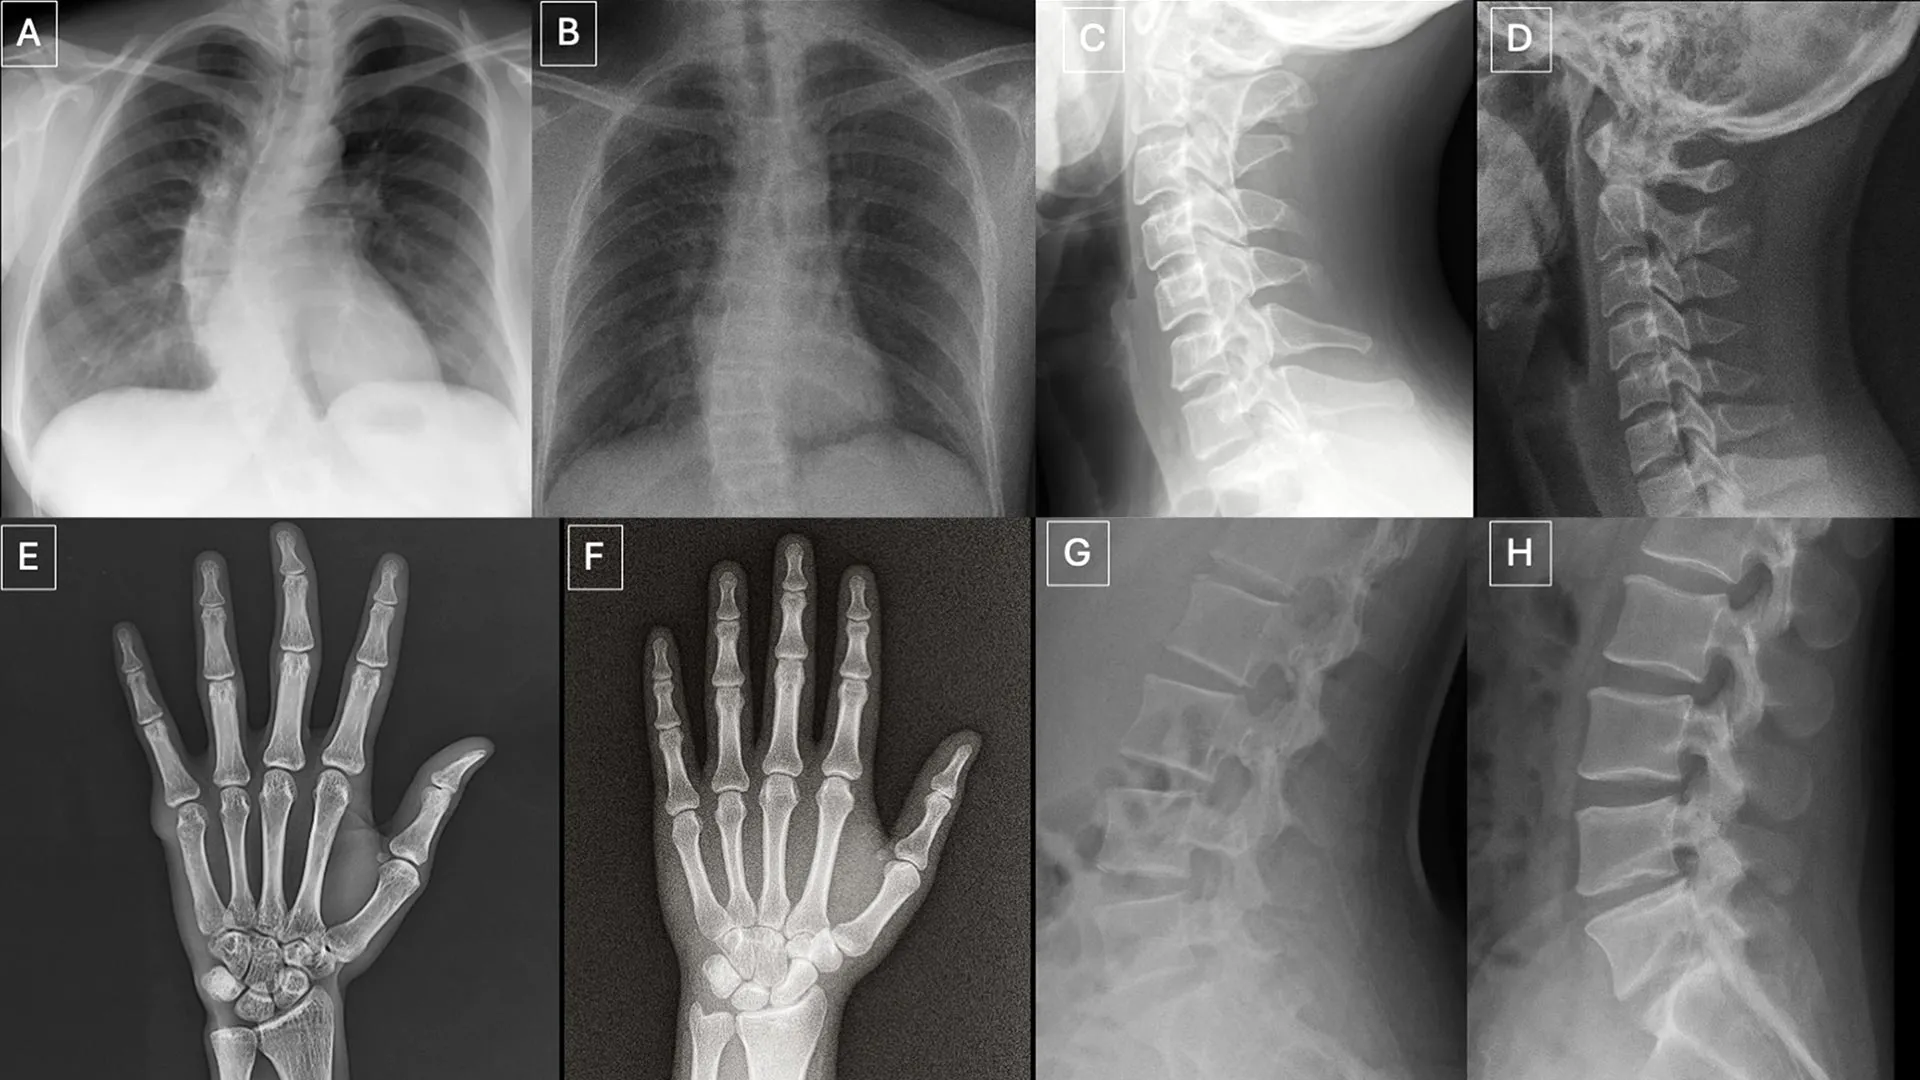

Os participantes avaliaram dois conjuntos de imagens distintos, sem sobreposição. Um conjunto continha uma mistura de imagens reais e radiografias geradas pelo ChatGPT de diferentes partes do corpo. O segundo conjunto focava em radiografias de tórax, com metade real e metade criada usando RoentGen, um modelo de difusão generativa de IA de código aberto desenvolvido por pesquisadores da Stanford Medicine.

Indícios Visuais em Radiografias Deepfake

Os pesquisadores identificaram vários padrões que podem aparecer em imagens sintéticas.

“Imagens médicas deepfake costumam parecer perfeitas demais,” comentou o Dr. Tordjman. “Os ossos são excessivamente lisos, as colunas são anormalmente retas, os pulmões são excessivamente simétricos, os padrões dos vasos sanguíneos são excessivamente uniformes, e as fraturas parecem incomumente limpas e consistentes, frequentemente limitadas a um lado do osso.”